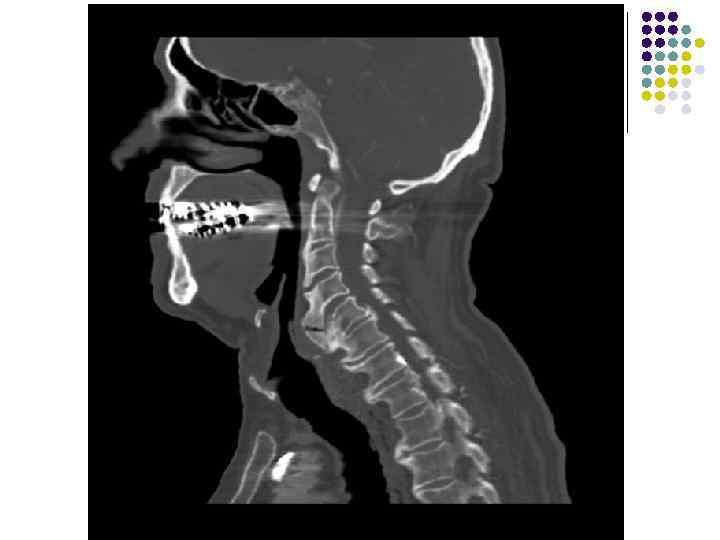

l На рентгенограмме шейного отдела позвоночного столба в боковой проекции определяется: выраженные дистрофические изменения за счет остеохондроза с преимущественными проявлениями в сегменте С 5 -6 – сужение и деформация межпозвонковых пространств, выраженный субхондральный остеосклероз, значительные костные разрастания по краям тел позвонков. Выпрямление физиологического лордоза. Признаки нарушения положения тела С 4 (симптом «распорки» )

l На рентгенограммах шейного отдела позвоночного столба в двух проекциях определяется комплекс выраженных дистрофических изменений с преимущественными проявлениями в сегментах С 5 -6 -7 в виде остеохондроза и выраженного спондилоза за счет неравномерного сужения межпозвонковых пространств, субхондрального отсеосклероза и костных разрастаний как по краям тел позвонков с продолжением плоскости замыкательной площадки, так и под передней продольной связкой с образованием мощного костного соединения. Положение тел позвонков правильное, деструктивных изменений нет.